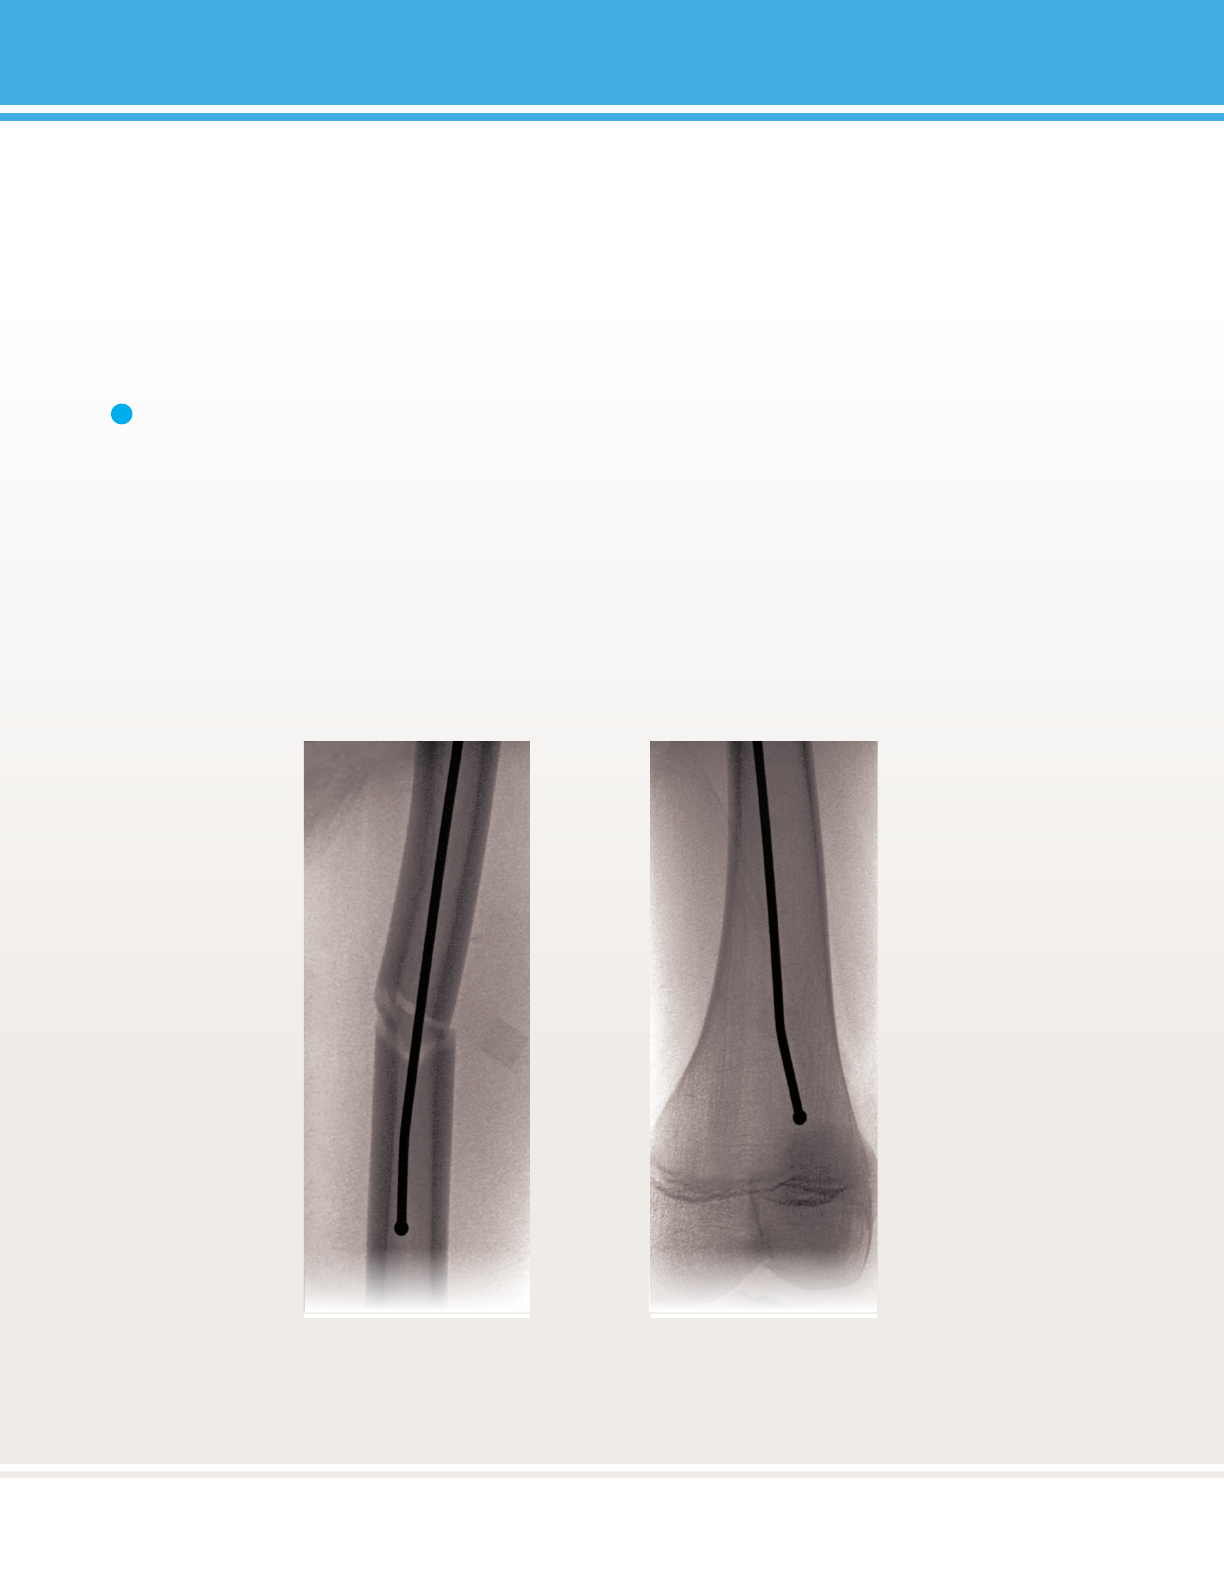

FIGURES 18a & 18b:

Note: Verify placement using AP and ML uoroscopy to ensure 2.7mm Ball Tipped Reaming Rod is in the distal

fragment.

CAUTION:

Do not advance 2.7mm Ball Tipped Reaming Rod into physis or joint space.